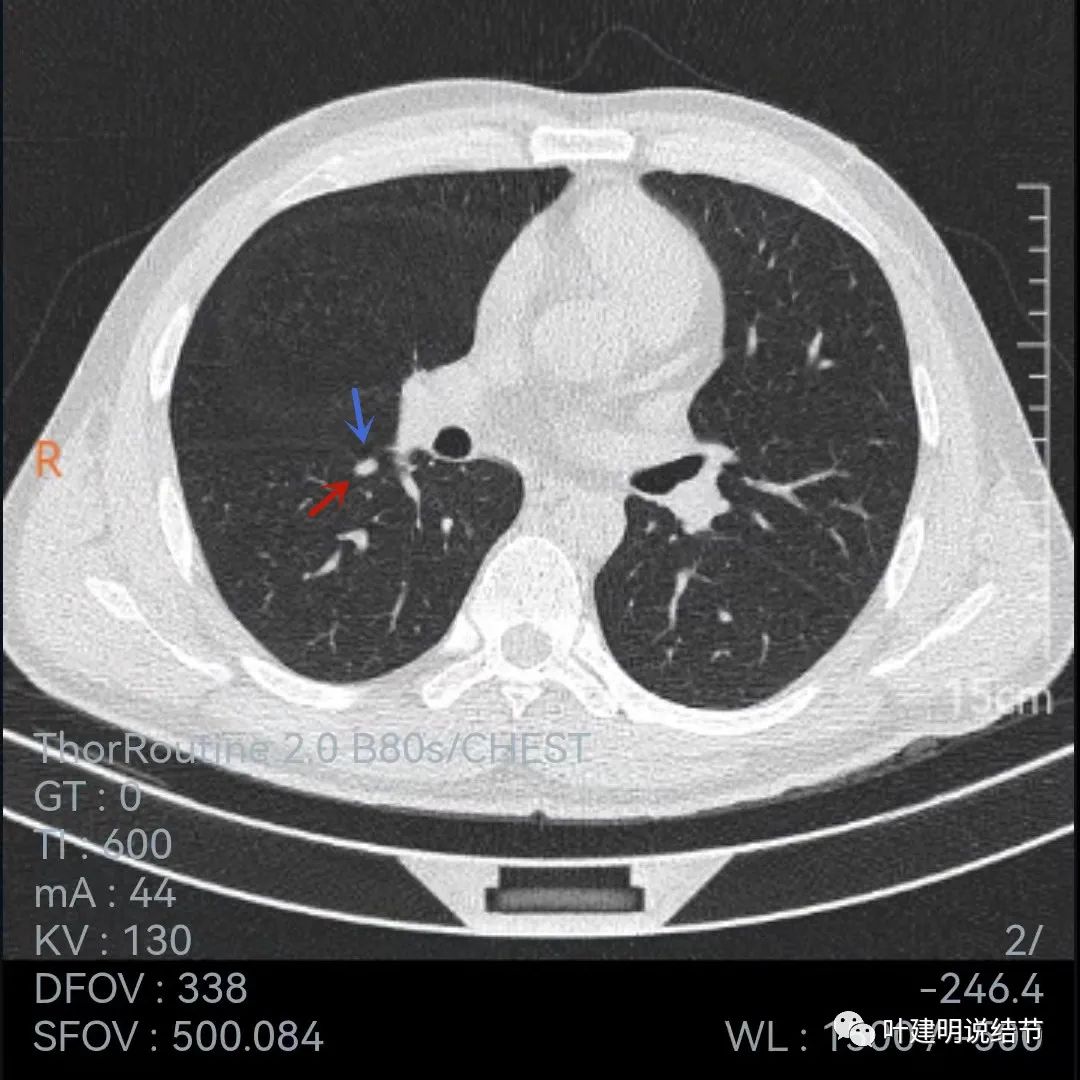

再来看薄层的,今年的薄层是1毫米一层的,去年是2毫米:

病灶胸膜凹陷更明显了,边缘不太平整(紫色箭头)

胸膜牵拉,伴病灶中间密度稍低

病灶膨胀性不够,感觉刺突相对较长,中间密度略低,边缘向内凹

上图黄色箭头示病灶中间密度要略低于周边部位,这与肉芽肿较为符合

整体还病灶似有进展,形态略有变化,但说典型的恶性样子好像又不太像。